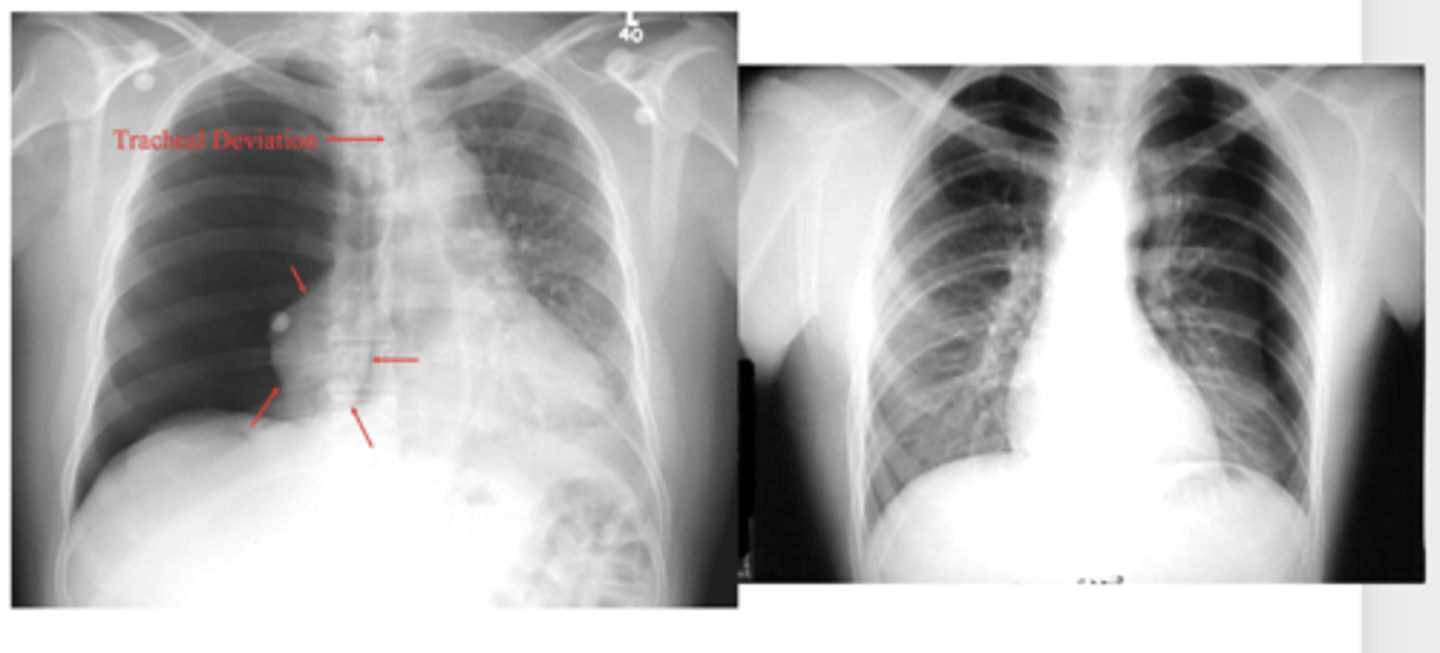

Shift of mediastinum

-if you're able to see t-spine in view, heart is not in the right place, likely laterally shifted

-hemidiaphragm

What is the main radiologic finding that differentiates tension and non-tension pneumothorax?

-mediastinal shift

-less density (darker)

-sharp line if non-tension pneumothorax

Seems like biggest difference is shift of mediastinum

Difference between tension and moderate pneumothorax